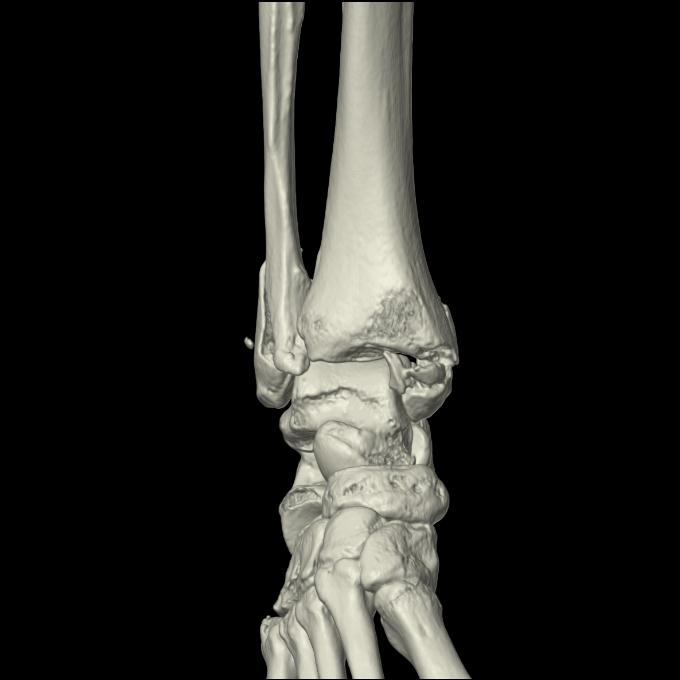

102755 1/4 2R 1/15 2R 右足関節 68歳女性 右三果脱臼骨折